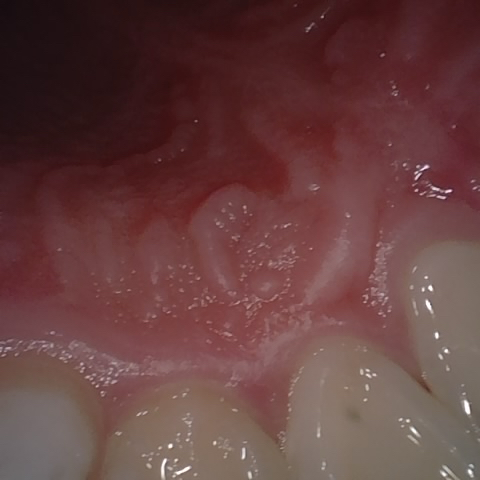

Annotated as "Good"